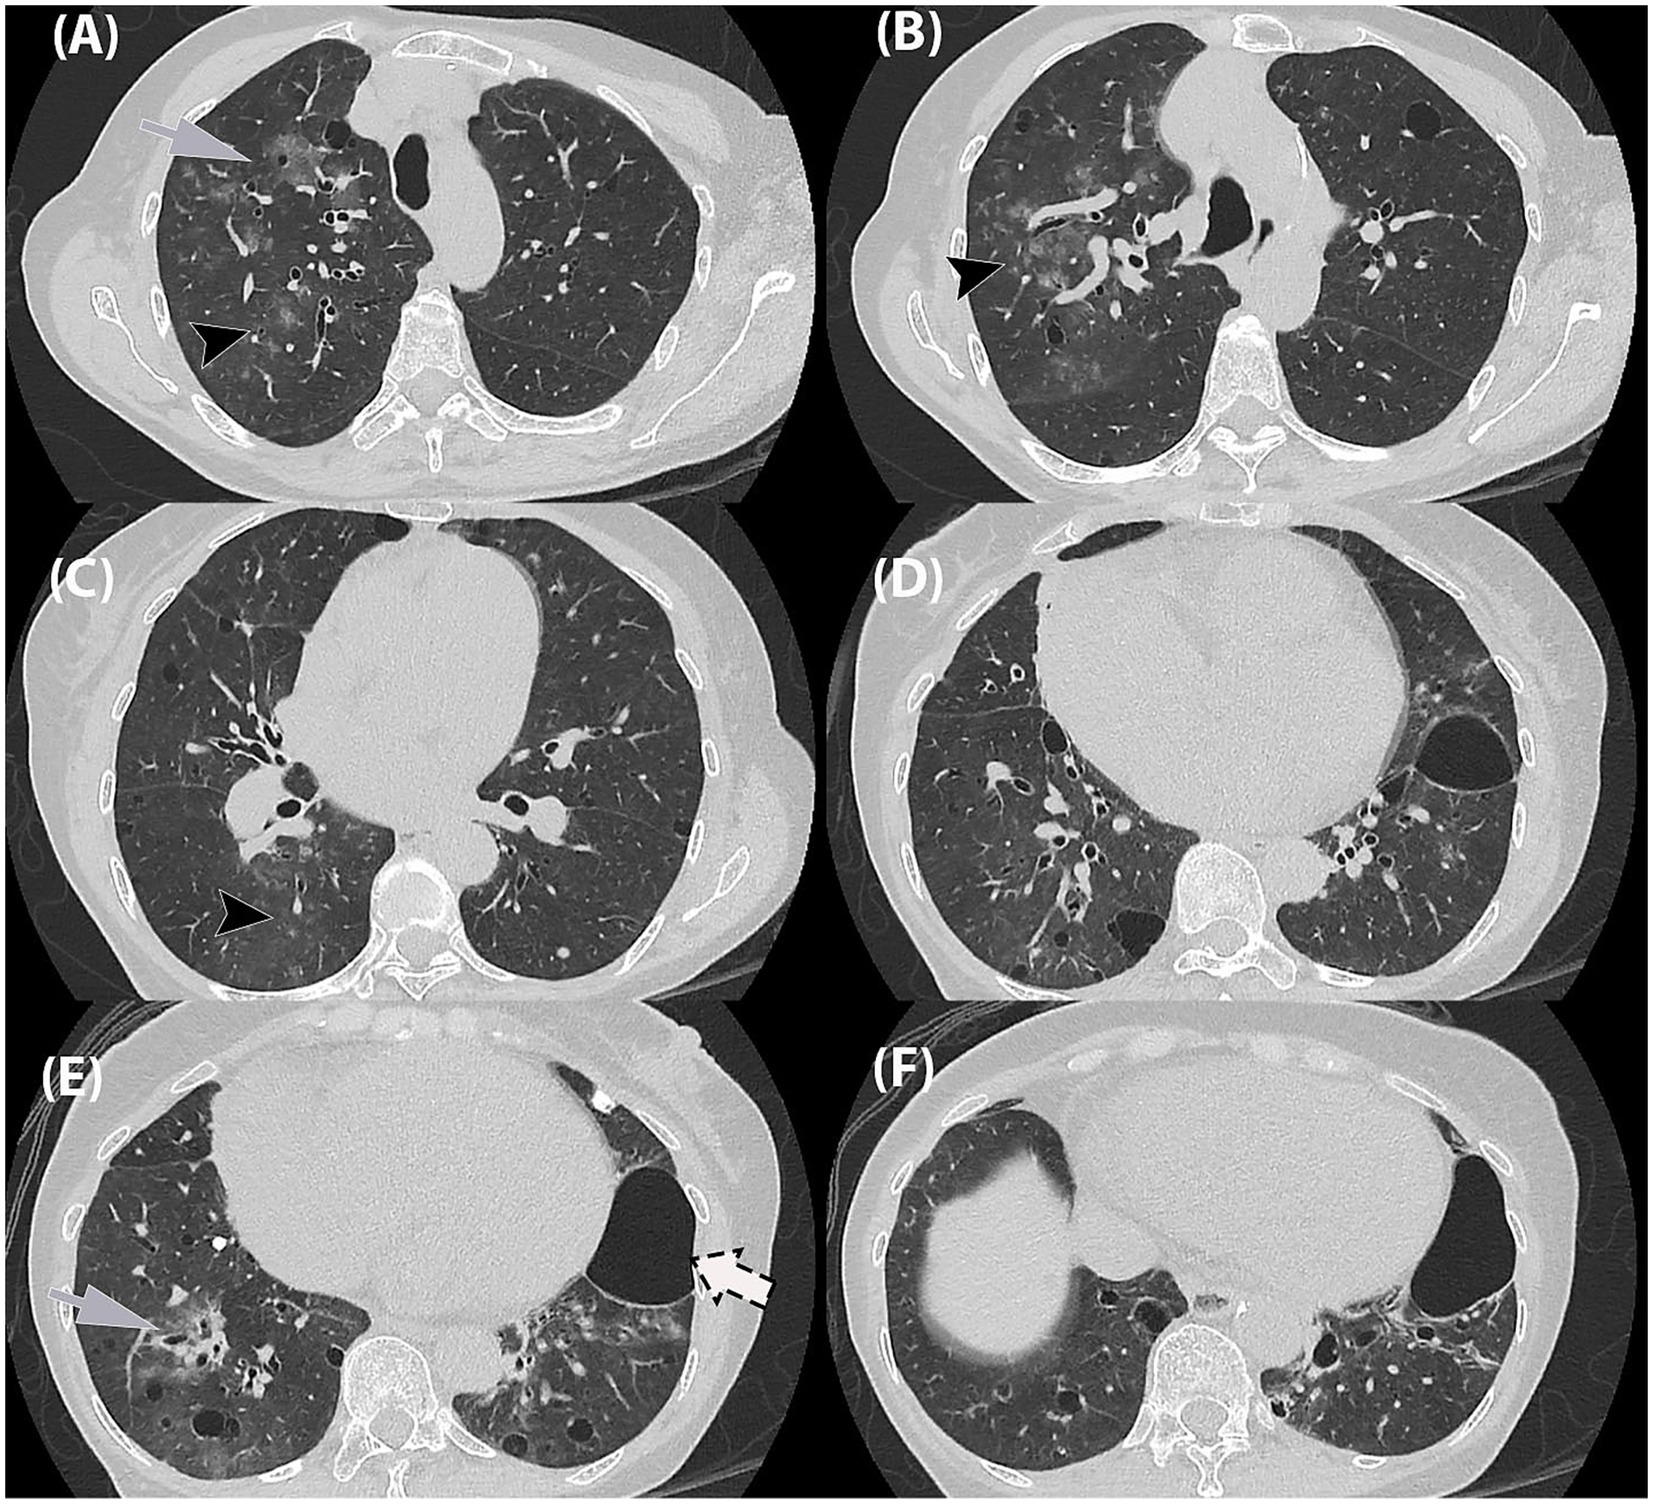

Given the progression in radiographic findings, a high-resolution CT (HRCT) thorax was performed on Day 4. The HRCT (Figure 2) showed patchy ground-glass opacities in a peribronchovascular distribution, with diffuse peribronchial wall thickening and mucus plugging, most pronounced in the right lung. Multiple lung cysts of varying sizes were scattered throughout the lung fields, predominantly in the right lung. A large cystic lesion measuring 5.8 × 4.0 × 4.7 cm was seen in the inferior lingular segment of the left lower lobe, which could be of a pneumatocele or subpleural bullae. Additionally, a calcified pleural plaque was present at the posterior segment of the right lower lobe.

Figure 2

Six-panel CT scan images of lung sections labeled A to F. Panels A, C, and E display abnormalities marked with arrows indicating areas of concern in the lungs. Panels B, D, and F show corresponding sections without highlighted areas, suggesting a comparison between affected and unaffected regions. Each panel provides a cross-sectional view of lung structures.

Figure 2. High-resolution chest tomography (HRCT) thorax in axial planes. (A,B) Ground-glass opacities in a bronchocentric distribution (grey arrow) as well as ground-glass centrilobular nodules in the right upper lobe (black arrowhead). (C,D) Similar ground-glass centrilobular nodules in right lower lobe (black arrowhead). (E,F) Ground-glass opacities in bronchocentric (grey arrow) distribution in bilateral lower lobes. (A–F) Randomly distributed thin-walled cysts of varying in bilateral lungs, (F) largest in left lower lobe (dashed-arrow).

At the time of imaging, routine serology and sputum cultures were negative, thereby leaving no microbiological evidence for the patient’s acute symptoms. High-resolution CT (HRCT) was therefore central in guiding the diagnostic workup. The scan revealed airway inflammation consistent with viral infection with no radiological feature of organizing pneumonia. This posed a diagnostic challenge as the HRCT findings led to several differential diagnoses. The lung nodules were indeterminate, while the cystic lesions raised the possibility of Pneumocystis jirovecii pneumonia (PCP), lymphoid interstitial pneumonia (LIP), or an underlying cystic lung disease. Although acute presentation and airway inflammation favored an infective etiology, alternative diagnoses could not be excluded. A post-treatment follow-up was recommended to monitor the cystic changes.